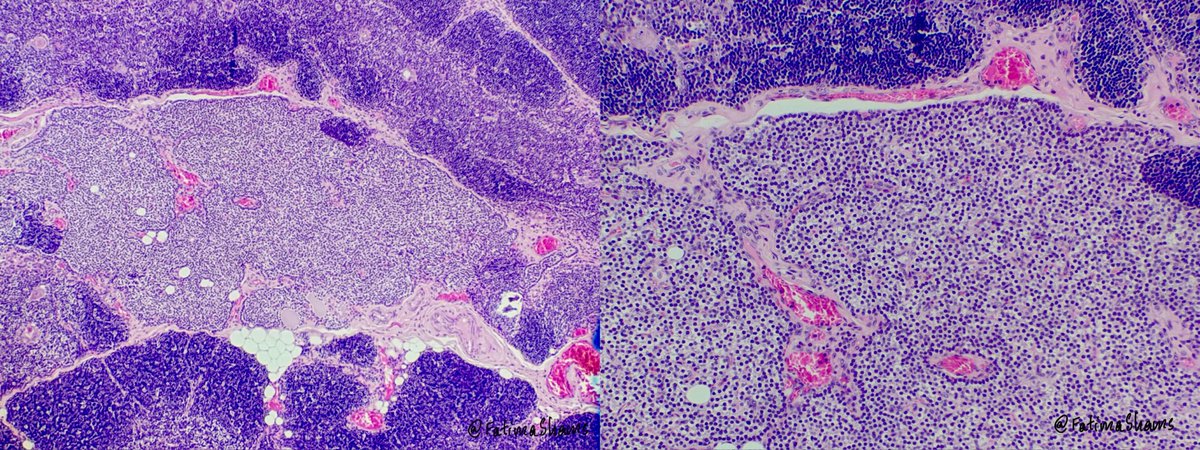

👉 74-year-old female with hematuria and bladder mass ⚓️ Urine cytology showed features suspicious for High-Grade Urothelial Carcinoma (HGUC) with: 🔬 Hyperchromatic crowded cell clusters 🔬 Single scattered atypical cells 🔬 Marked pleomorphism, high N:C ratio 🔬 Irregular nuclear membranes & coarse chromatin 💎 Biopsy confirmed High-Grade Papillary Urothelial Carcinoma showing fused/complex papillae, loss of maturation, diffuse cytologic atypia, and numerous mitoses. A nice histocytologic correlation case highlighting the importance of urine cytology in detecting HGUC. #PathTwitter #Cytopathology #Uropath #Surgpath #UrineCytology #HGUC #UrothelialCarcinoma #Histopathology #MedEd #Pathology